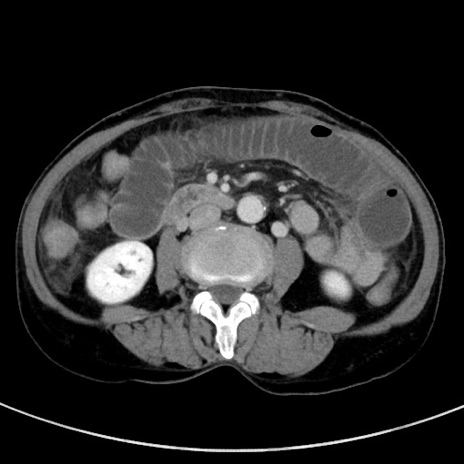

症例23(横断像)

【症例】70歳代女性

【主訴】下腹部痛・嘔吐

【現病歴】2日前より腹痛あり。昨日嘔吐あり。症状改善しないため来院。

【既往歴】胃GISTに対して胃部分切除後。

【身体所見】BT 37.1℃、BP 128/77mmHg、腹部:平坦・軟、下腹部に圧痛あり。

【データ】WBC 10200、CRP 0.31